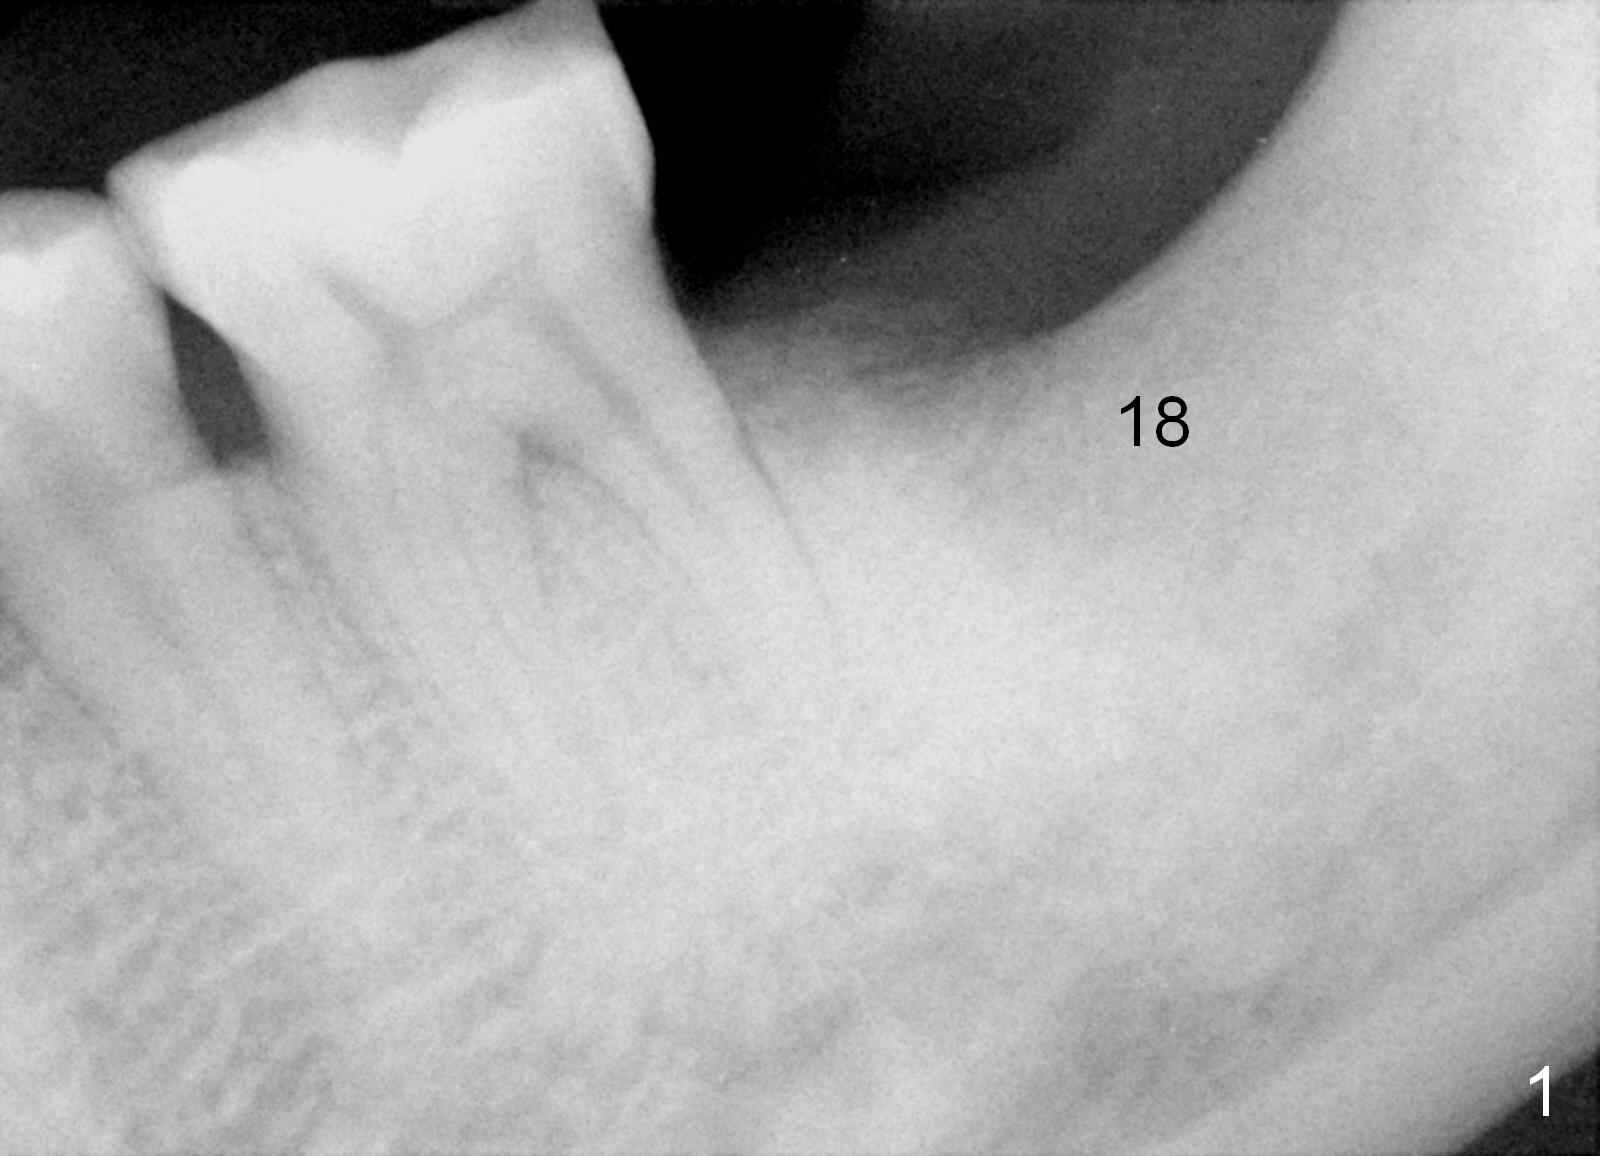

The patient has never made an appointment for perio maintenance since implant placement. The most recent PA shows peri-implant bone loss increases mesially and extends distally (Fig.5 arrowheads). The open contact remains (*). Although there is no gingival erythema around the implant, the pockets appear to be deep.

It appears that a new crown is required to fix the open contact and that debridement of the coronal implant threads with bone graft is necessary.